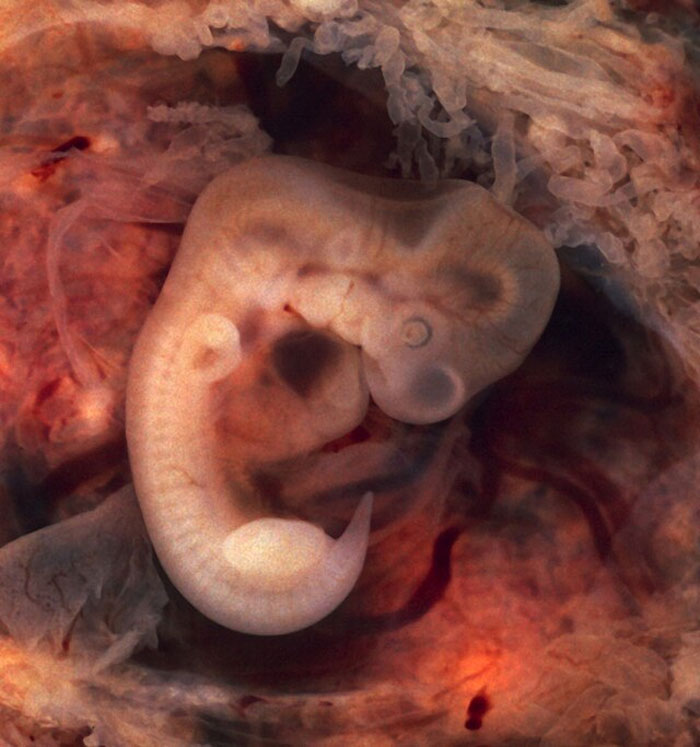

No es una autopsia propiamente dicha, pero cuando trabajaba como auxiliar de laboratorio, recibimos algo que nos dejó perplejos tanto al médico a cargo como a mí. Tras muchos intentos por entender qué era y analizar diferentes secciones, finalmente me di cuenta de que era un embrión bastante malformado. La diminuta cabecita todavía me rompe el corazón. He visto muchas anomalías extrañas y he tenido diferentes órganos en mis manos, pero ese era un ser humano completo que jamás podría haber llegado a la vida. Te impacta de una manera diferente.